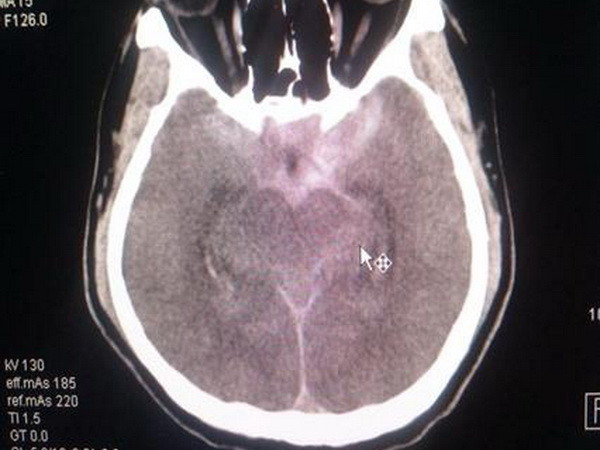

Cứu sống bệnh nhân hai lần ngưng tim do vỡ túi phình mạch máu não ảnh 1Hình ảnh CT sọ của bệnh nhân trước can thiệp. (Ảnh: TTXVN phát)

Kết quả CT-scan sọ não và DSA mạch máu não cho thấy bệnh nhân bị xuất huyết khoang dưới nhện do vỡ túi phình đốt sống bên phải.

Sau hơn 20 ngày điều trị tích cực, ngày 21/5, kết quả CT scan sọ não cho thấy bệnh nhân đã hết hiện tượng chảy máu não, được chỉ định ngưng thở máy, rút ống thở, tri giác cải thiện rõ, bệnh nhân tỉnh, trả lời và thực hiện y lệnh chính xác, hết sốt.